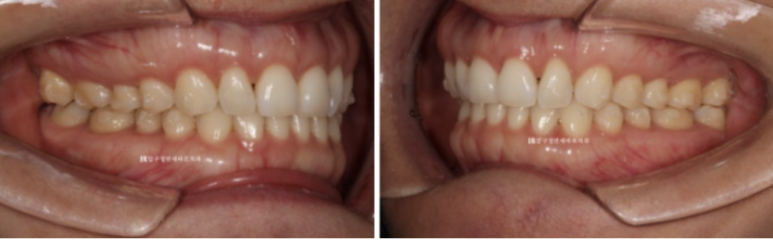

중심선 불일치 그리고 오른쪽의 맨 뒤 큰어금니 바깥으로 나가 있는 가위교합이 정면에서도 잘 보입니다.

23.07

오른쪽 맨 뒤 큰 어금니의 가위교합이 보이고 왼쪽은 송곳니와 앞니 벌어진 공간이 보입니다.

인비절라인 라이트로 이 모든 것을 해결하고 치료에 들어갑니다.